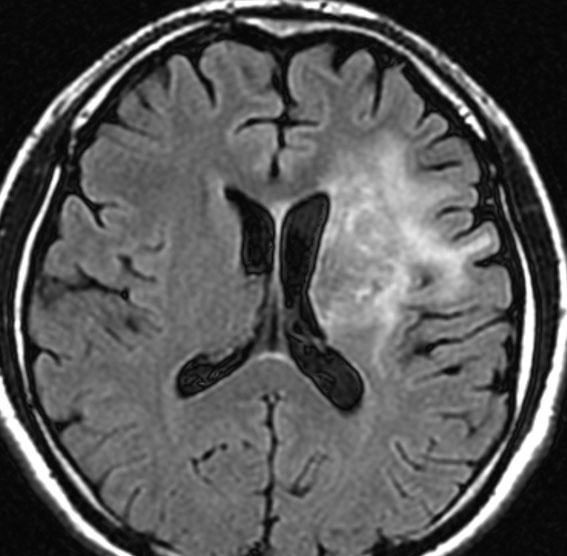

放射線治療後7週目

フレア画像です。腫瘍サイズが増大しています。もともと腫瘍周辺浮腫はなかったのですが大脳基底核と視床に浮腫が出現しています。スード・プログレッションの始まりです。

放射線治療後9週目

フレア画像です。たった2週間で脳浮腫が高度の脳浮腫となっています。失語症と右片麻痺と認知機能低下が生じました。ステロイド剤とグリセリンの点滴を行いました。